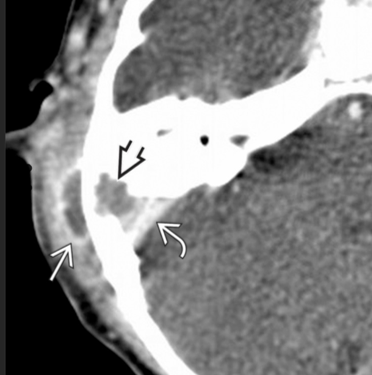

acquired cholesteatoma in the epitympanum

which semicircular canal gets eroded in the setting of an acuired cholesteatoma in the epitymapnic space?

lateral semicircular canal